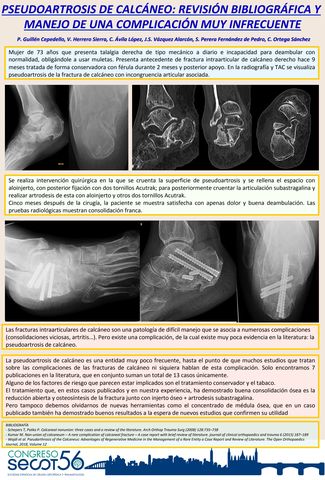

PSEUDOARTROSIS DE CALCÁNEO: REVISIÓN BIBLIOGRÁFICA Y MANEJO DE UNA COMPLICACIÓN MUY INFRECUENTE

Título: PSEUDOARTROSIS DE CALCÁNEO: REVISIÓN BIBLIOGRÁFICA Y MANEJO DE UNA COMPLICACIÓN MUY INFRECUENTE

Autores:

PEDRO GUILLÉN CEPEDELLO, VIRGINIA HERRERO SIERRA, CRISTINA ÁVILA LÓPEZ, JUAN SEBASTIAN VAZQUEZ ALARCON, SANTIAGO PERERA FERNÁNDEZ DE PEDRO, CARLOS ORTEGA SANCHEZ

Ver eposter